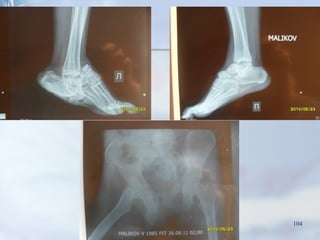

Пациент М. 1985 г.р. :

Травматический шок 1 степени. (PTS-28 баллов)

104

I этап

Наложение АВФ на таз, обе голени и обе стопы, ПХО открытого перелома

костей стопы, наложение ВАК системы, открытое вправление таранной

кости справа с фиксацией спицами, вправление таранной кости справа с

фиксацией спицами.